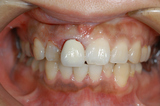

自転車で転倒し前歯が根本から折れてしまい、抜歯に至ったケース

このケースは感染していないので、抜歯と同時にインプラント埋入

埋入後、3か月で終了